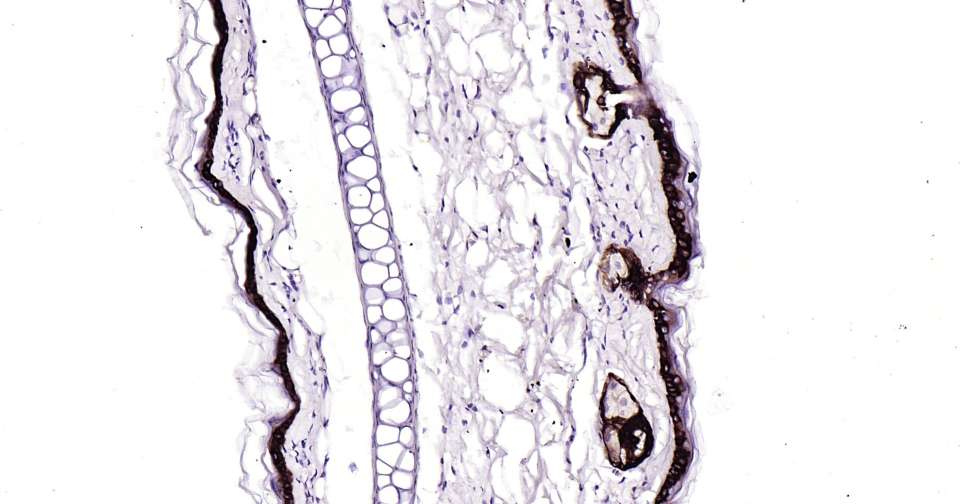

Immunohistochemical analysis of paraffin embedded mouse skin tissue slide using IHC0403M (Mouse Cytokeratin 15 IHC Kit).